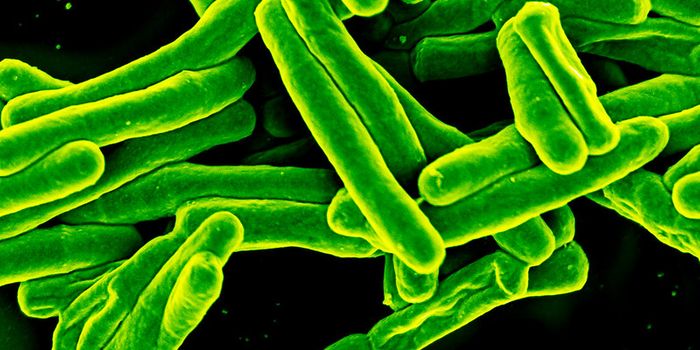

DEC 08, 2024Clinical & Molecular DXA rapid diagnostic test for tuberculosis (TB) has been approved for the first time by the World Health Organization (WHO ...